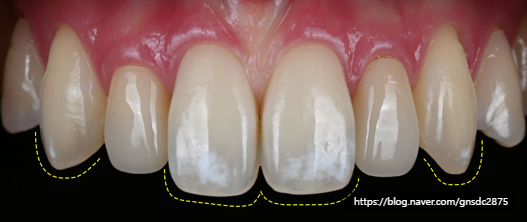

#CASE 02

백색반점이 있는 길이가 다른 앞니

다음 환자분도 양앞니의 백색반점과

미세하게 다른 치아 길이를

앞니통합치료 뉴티스로 개선하였습니다.

#CASE 03

세번째 케이스도 마찬가지로

양앞니와 옆치아까지 번진 백색반점을

뉴티스 반점치치료로 개선하고

울퉁불퉁 고르지 못한 치아 끝을

뉴티스 치아성형을 통해 고르게 개선하였습니다.